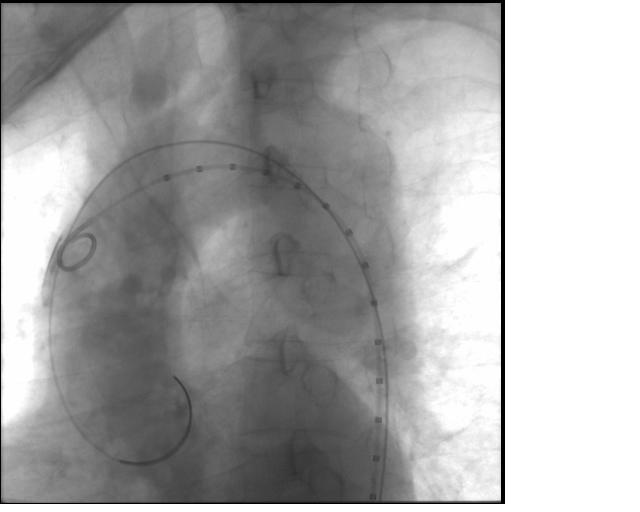

EVAR